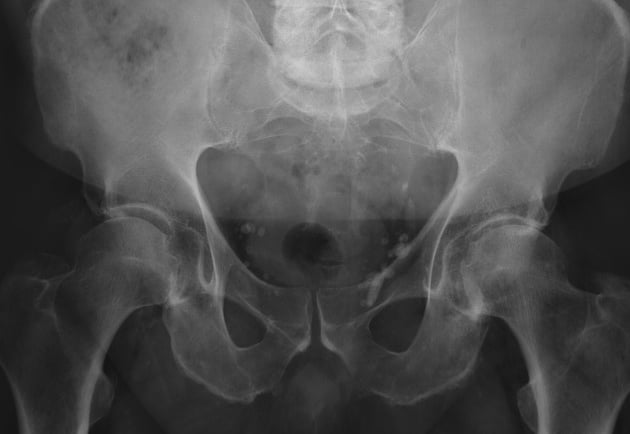

Para determinar la causa exacta del dolor, se realiza una evaluación clínica detallada, analizando la movilidad, la estabilidad asi como pruebas especificas para identificar las causas probables del dolor. En muchos casos, se complementa el diagnóstico con estudios de imagen para observar el estado de los huesos, los cartílagos y los tejidos blandos, así como pruebas de laboratorio en caso de sospecha de enfermedades inflamatorias o metabólicas.